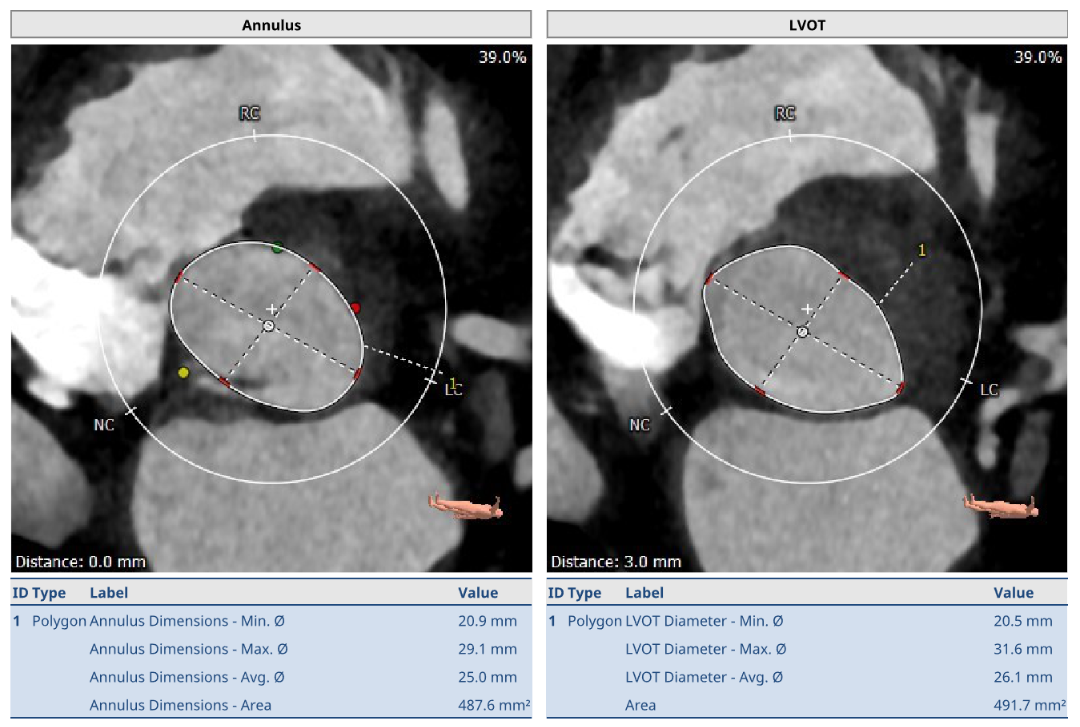

手术团队术前经充分的食道超声及心脏CTA详尽评估患者病情、外科手术风险,通过CT重建测量瓣环直径、左室流出道面积、房间隔穿刺位置等确定手术策略与解剖入路,最终决定采用二尖瓣经导管瓣中瓣手术,选择瓣架较短,可应用于各个不同瓣位的RENATUS®球扩式经导管主动脉瓣。

患者既往植入27# 佰仁思牛心包瓣,选用27# RENATUS®球扩式经导管主动脉瓣,术前模拟植入测得Neo-LVOT面积217.3mm²。

手术采用经心尖入路,术中植入27# RENATUS®球扩式经导管主动脉瓣。瓣膜植入位置理想、功能表现出色,无明显瓣中及瓣周反流,患者症状明显改善。